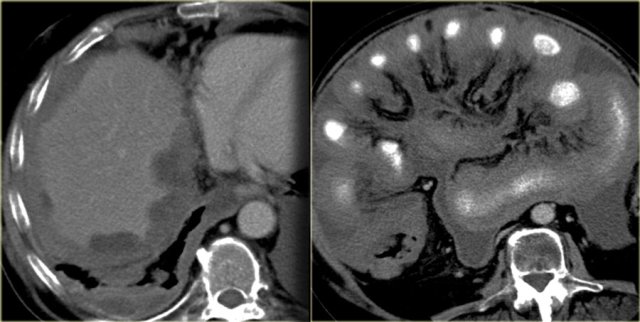

Mesenteric fibromatosis - Desmoid

Mesenteric fibromatosis is also known as intra-abdominal fibromatosis, abdominal desmoid or desmoid tumor.

On the left a 33-year-old man who complains of an increasing abdominal girth, abdominal fullness, and a palpable abdominal mass.

First study the images on the left and continue with the MR.

Look for some imaging features that are helpful in the differential diagnosis.

First of all this is a well circumscribed lesion with a low density on CT.

There is some enhancement around the lesion and there are some small strands of enhancement within the lesion.

On MR there is a low signal on T1 as we would expect.

On T2 there is relatively high signal.

In combination with the low density on CT this tells us that there is mucin within the lesion.

This finding is very suggestive of the diagnosis of mesenteric fibromatosis.

Mesenteric fibromatosis - Desmoid (2)

The enhancement on MR is more intense compared to the enhancement on CT.

On CT the low density of the mucin stands out, but on MR we can appreciate the enhancement better.

It tells us that the lesion is well vascularized.

Mesenteric fibromatosis or desmoid is a benign proliferative process that is locally aggressive and can recur, but it does not metastasize.

The small bowel mesentery is the most common site.

13% of patients have familial adenomatous polyposis (FAP).

On the left images of another patient with mesenteric fibromatosis.

Notice that this lesion is not of low attenuation.

This lesion has a more collagenous or fibrous stroma.

So there are two distinct patterns.